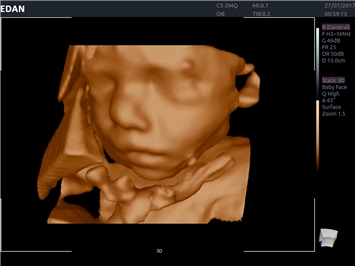

• 3D/4D-визуализация с автоматическим редактированием объема (eFace)

• Автоматизированные измерения в акушерстве

• Акушерства и гинекологии

3D/4D:

Да

Color 3D: